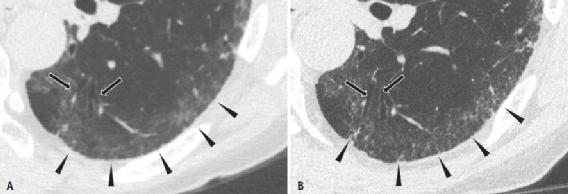

肺和肌肉骨骼成像中的许多诊断任务依赖于CT扫描大身体区域同时显示小结构的能力。因此,PCD-CT的空间分辨率的提高可能有助于肺和肌肉骨骼成像中的许多诊断任务。例如,PCD-CT由于其较高的空间分辨率,显示了与间质性肺疾病相关的详细和细微的成像结果。Inoue等人最近证明,在已知或疑似常见间质性肺炎的患者中,PCD-CT增加了阅片医生对主要成像结果的信心,如毛玻璃不透明度、网状结构和马赛克图案(图2)。PCD-CT还改善了远端支气管和支气管壁的可视化。对于肺和肌肉骨骼应用,通过使用更高分辨率的重建卷积核,通常通过使用更薄的切片来实现较小结构的改进可视化。

图2 74岁男性,临床诊断为特发性非特异性间质性肺炎,采用临床常规方案在常规EID-CT(A)和PCD-CT(B)上进行扫描。

A、B 与常规CT相比,PCD-CT显示右胸膜下右下叶的精细网状结构(箭头,B),常规CT显示该区域的毛玻璃样阴影(箭头,A)。光子计数探测器比常规CT更清晰地显示牵引性支气管扩张(箭)。